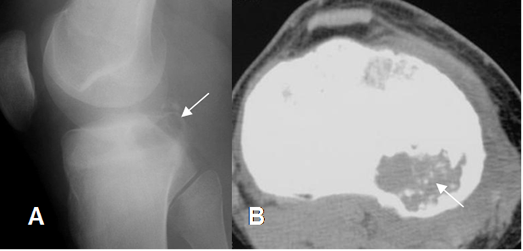

Fig 82. Condroblastoma.

A: Rx lateral y B: TAC axial. Lesión lítica y epifisiaria en la tibia proximal, con calcificaciones puntiformes de origen condroide, por condroblastoma.